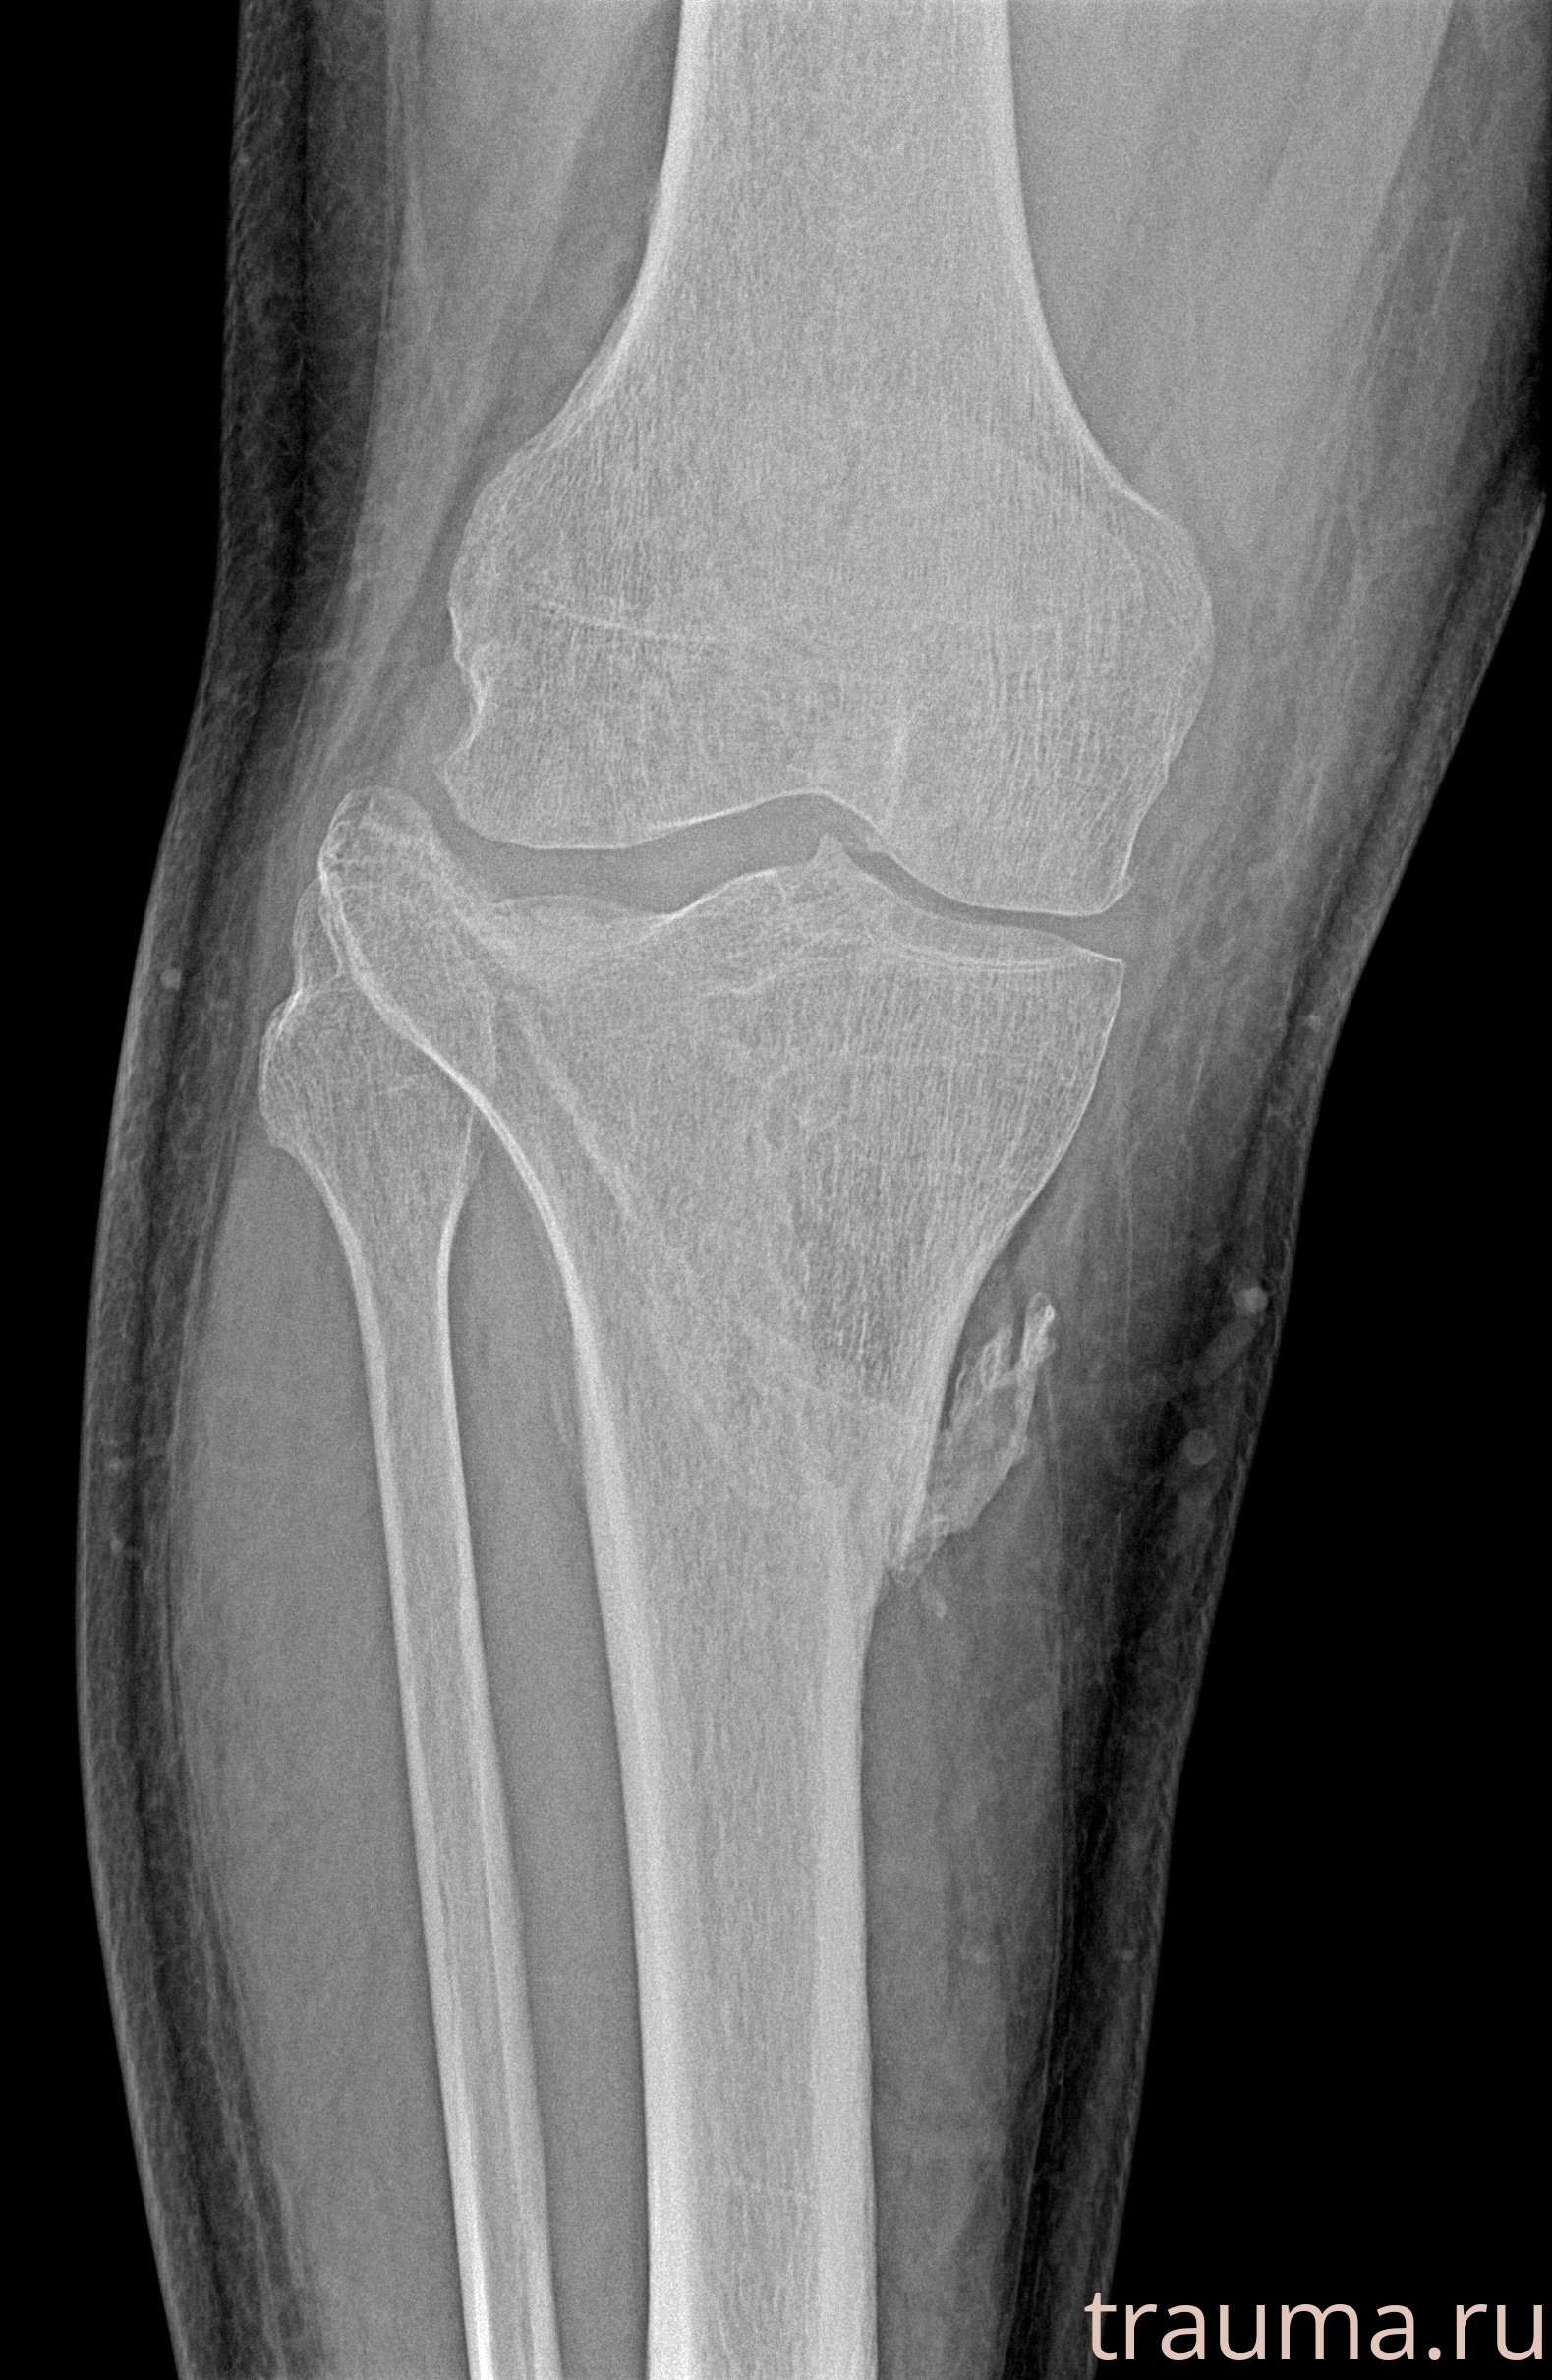

Рентгенограммы

Рентген на дому: по вашему адресу приезжает врач-рентгенолог, травматолог-ортопед с мобильным рентгеновским аппаратом, проводит диагностику травмы или заболевания, делает необходимые рентгенограммы, дает рекомендации по дальнейшему лечению. Получить качественные снимки в домашних условиях возможно благодаря уникальной методике, разработанной МосРентген Центром для института  Склифосовского